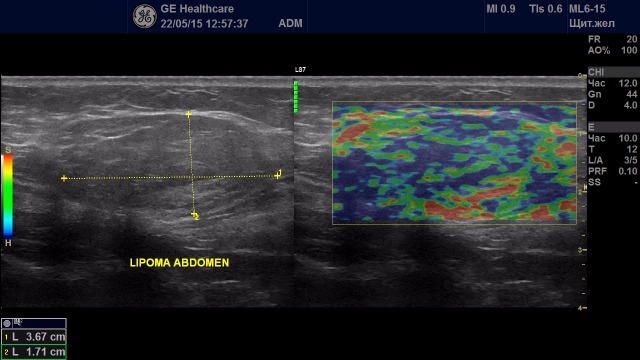

Образование с удовлетворительной эластичностью